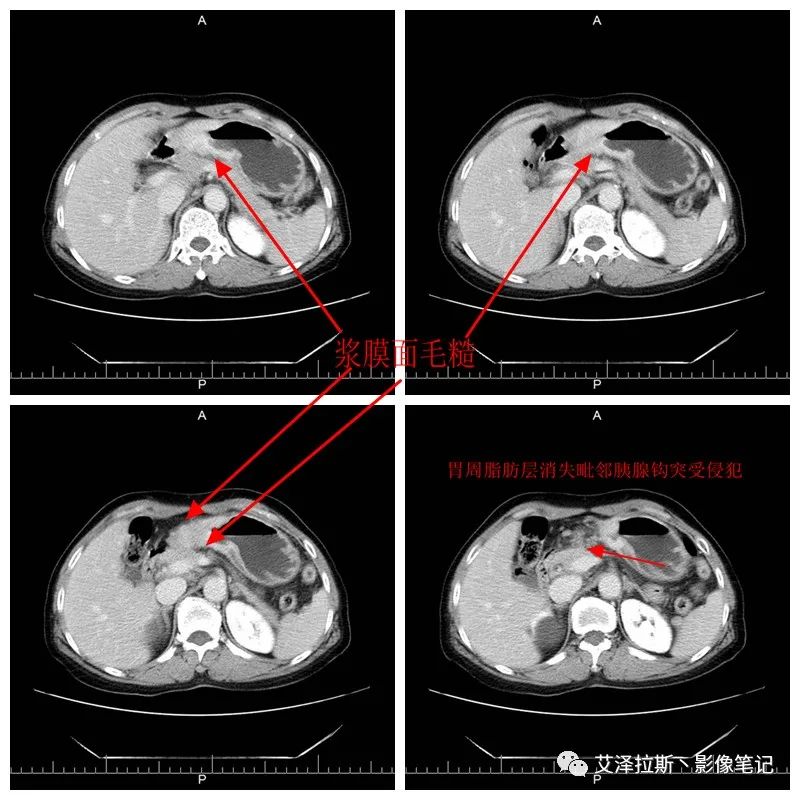

【影像所見】 胃竇部狹窄,胃壁環形增厚,小彎側見一巨大潰瘍,周圍伴“環堤征”,漿膜面不完整,胃周脂肪見網格狀條索影,病灶與肝臟左葉、胰腺鉤突脂肪間隙消失,增強掃描病灶明顯強化。引流區內約15個區域淋巴結受累。

【診斷意見】 胃竇部胃癌(T4N3期) 該病例腫塊突破漿膜層,與肝臟左葉、胰腺鉤突分界不清,脂肪界面消失,定為T4期; 受累及的淋巴結為15個區域,定為N3; 有無遠處轉移尚不明確,所以M期暫時無法確定。